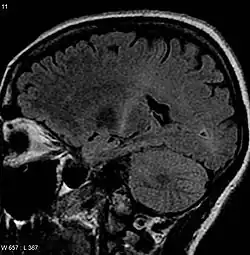

Because symptoms of ALS can be similar to those of a wide variety of other, more treatable diseases or disorders, appropriate tests must be conducted to exclude the possibility of other conditions. One of these tests is electromyography (EMG), a special recording technique that detects electrical activity in muscles. Certain EMG findings can support the diagnosis of ALS. Another common test measures nerve conduction velocity (NCV).[92] Specific abnormalities in the NCV results may suggest, for example, that the person has a form of peripheral neuropathy (damage to peripheral nerves) or myopathy (muscle disease) rather than ALS. While a magnetic resonance imaging (MRI) is often normal in people with early-stage ALS, it can reveal evidence of other problems that may be causing the symptoms, such as a spinal cord tumor, multiple sclerosis, a herniated disc in the neck, syringomyelia, or cervical spondylosis.[3]